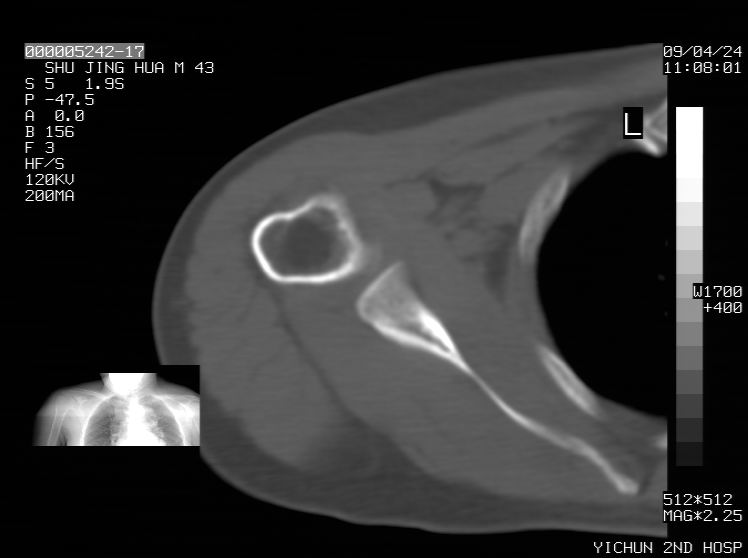

标题: CT19569:请会诊,女50岁,右肩疼痛数月 [打印本页]

标题: CT19569:请会诊,女50岁,右肩疼痛数月

钙化性肌腱炎

是指钙盐沉积在变性肌腱中的一种无菌性炎症,常见于肩关节的肩袖肌腱,引起肩部疼痛和活动受限。分为急性和慢性两种类型,急性型有肩关节突然出现急性疼痛的发作史,夜间可痛醒。